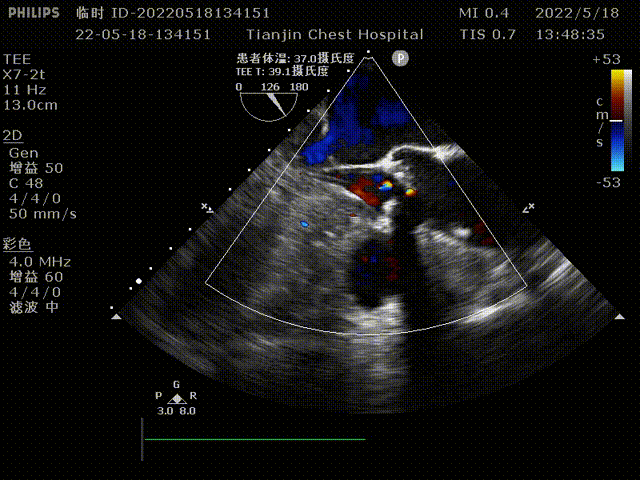

术前超声心动图:

LVEF:61%;PPG:30mmHg;LA:42mm;RA:30mm;LV:52mm;

RV:30mm;Amax:6.3m/s;mPG:95mmHg;AVA:0.6cm²。

主动脉瓣重度狭窄;

主动脉轻度反流;

二尖瓣及三尖瓣轻度反流。

术前TEE检查:TEE多普勒检查